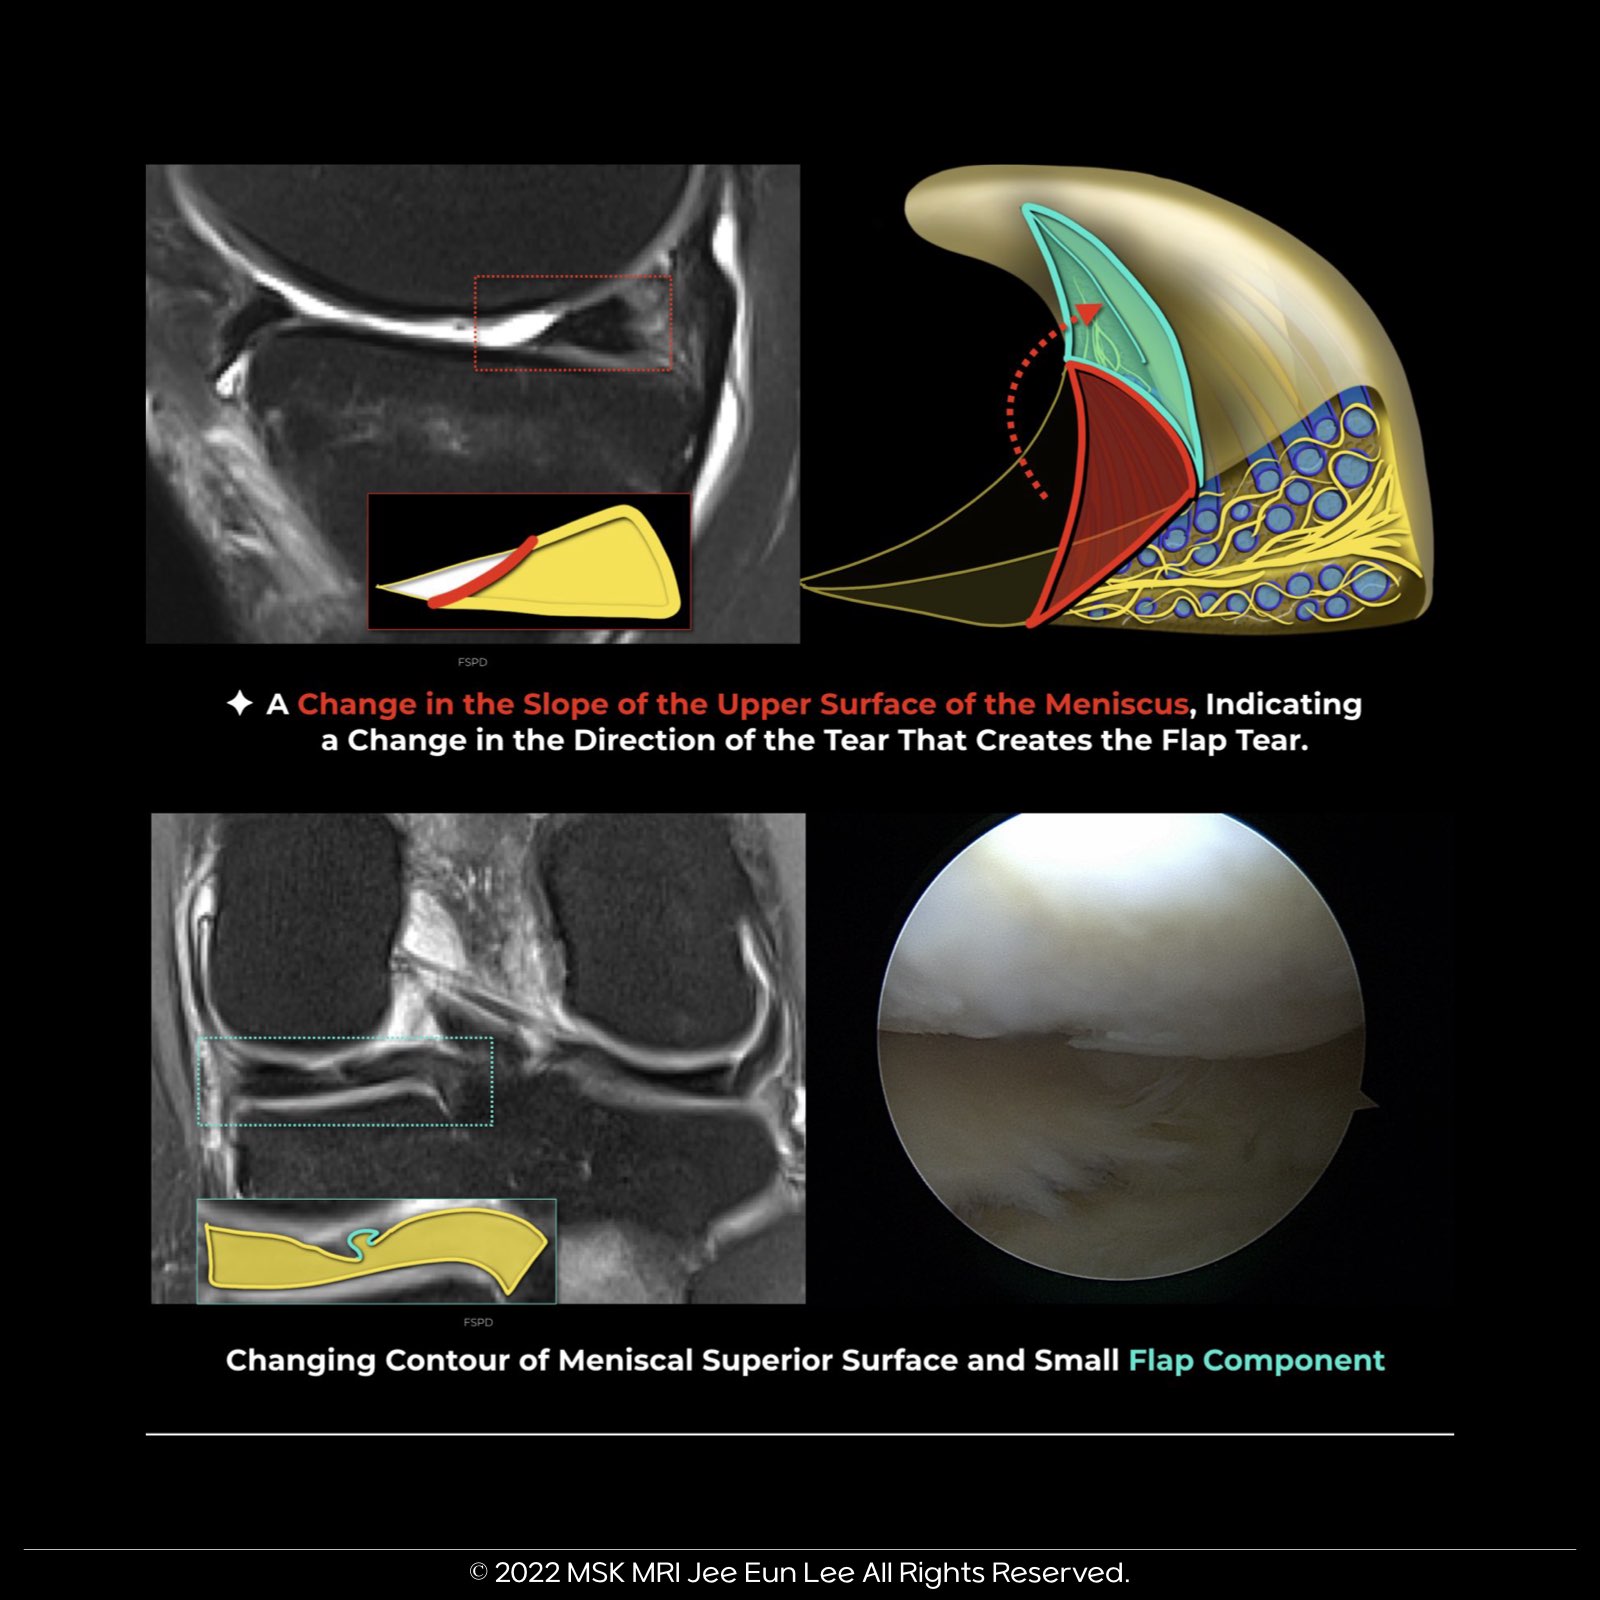

When dealing with meniscal flap tears, keep an eye out for a crucial indicator – a change in the slope of the meniscus's superior surface. This change signals a shift in the tear's direction, forming the characteristic flap.

Flap tears often exhibit a shifting slope in the meniscal surface, denoted as the "changing slope sign."

For clarity, the corresponding axial image shows a free edge flap component (component not displaced). This component can also display a changing slope contour on its superior surface.